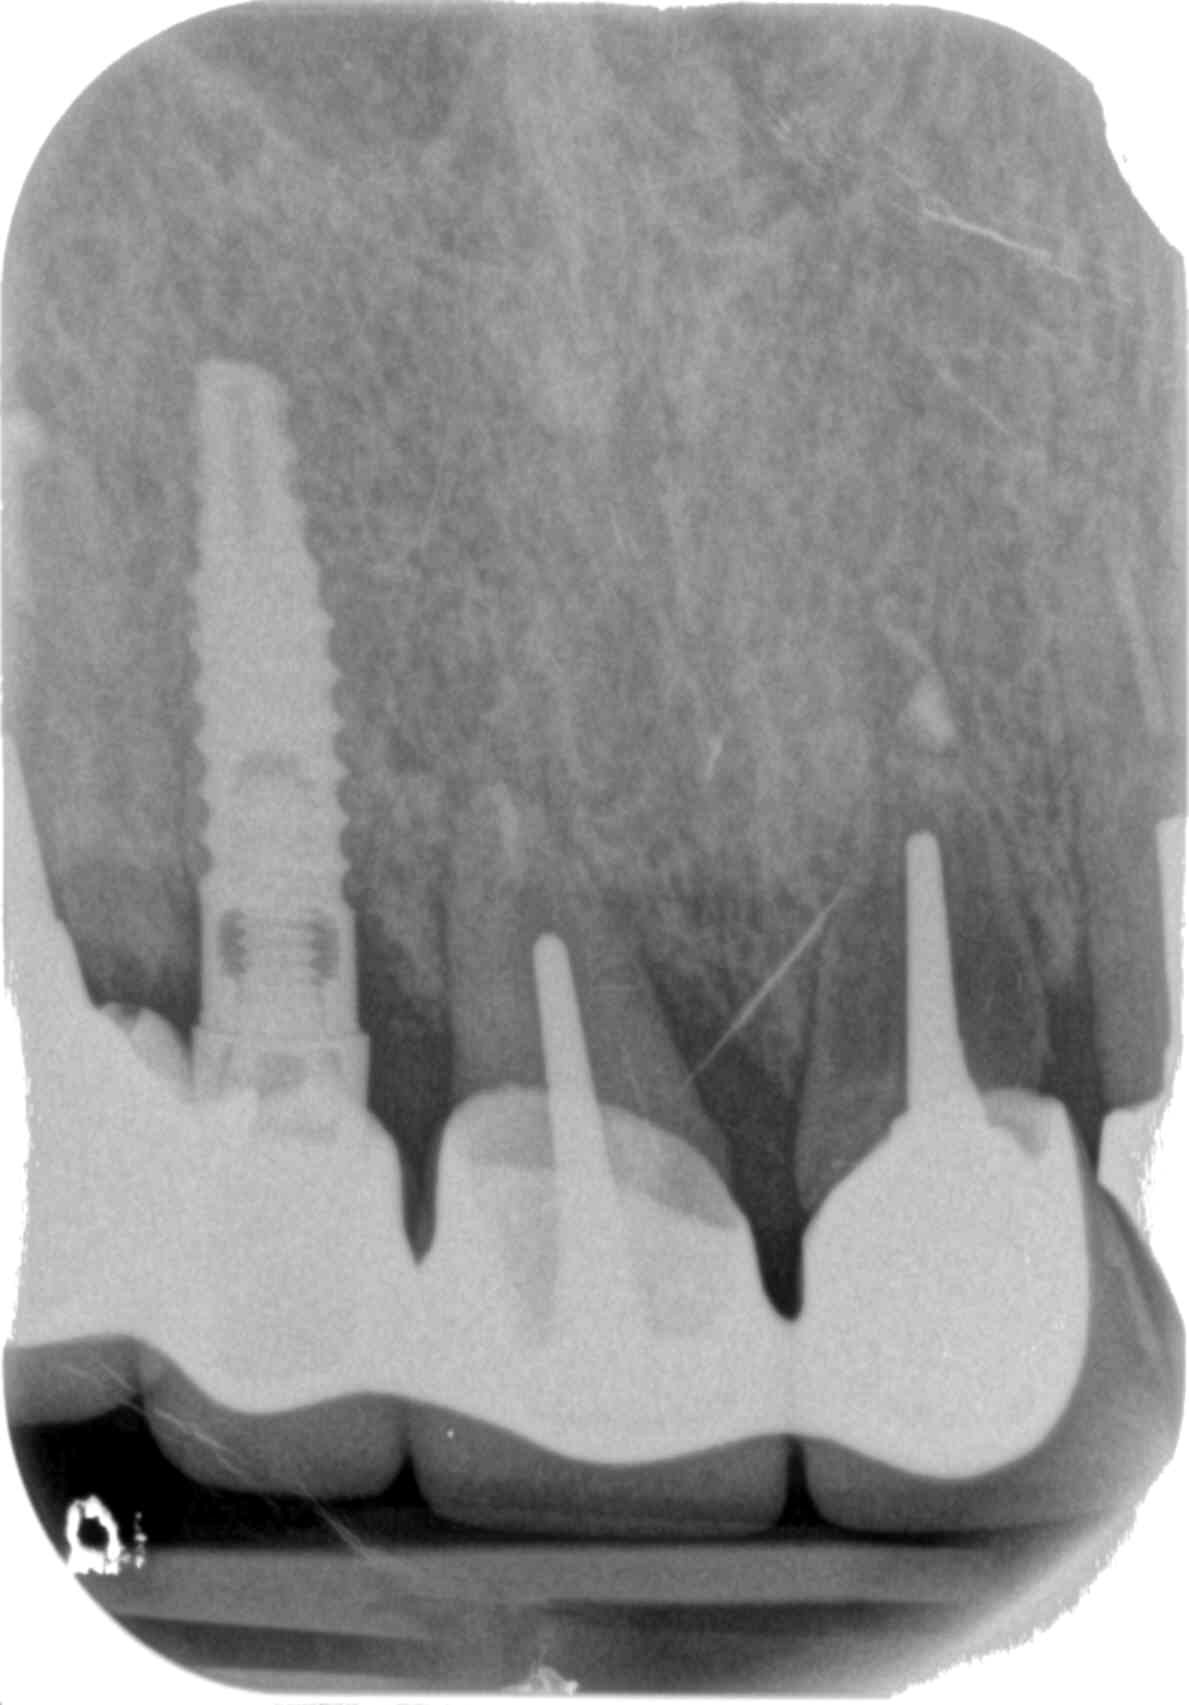

Me gustaria conocer la marca y referencias de estos implantes colocados para en un principio rehabilitar un 36, fueron colocados en francia hace unos 6-7 años.nunca han sido rehabilitados. gracias!!

Buenas tardes, Solicito por favor, averiguar la marca del Implante en posición de la pieza 37. Muchas Gracias.